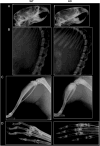

Methods and results: By whole exome sequencing in a boy with OSMD, we identified a homozygous 7 bp deletion (c.5938_5944delGAGTGGT) in the LRRK1 gene. His skeletal phenotype recapitulated that seen in the Lrrk1-deficient mouse. The shared skeletal hallmarks included severe sclerosis in the undermodelled metaphyses and epiphyseal margins of the tubular bones, costal ends, vertebral endplates and margins of the flat bones. The deletion is predicted to result in an elongated LRRK1 protein (p.E1980Afs*66) that lacks a part of its WD40 domains. In vitro functional studies using osteoclasts from Lrrk1-deficient mice showed that the deletion was a loss of function mutation. Genetic analysis of LRRK1 in two unrelated patients with OSMD suggested that OSMD is a genetically heterogeneous condition.